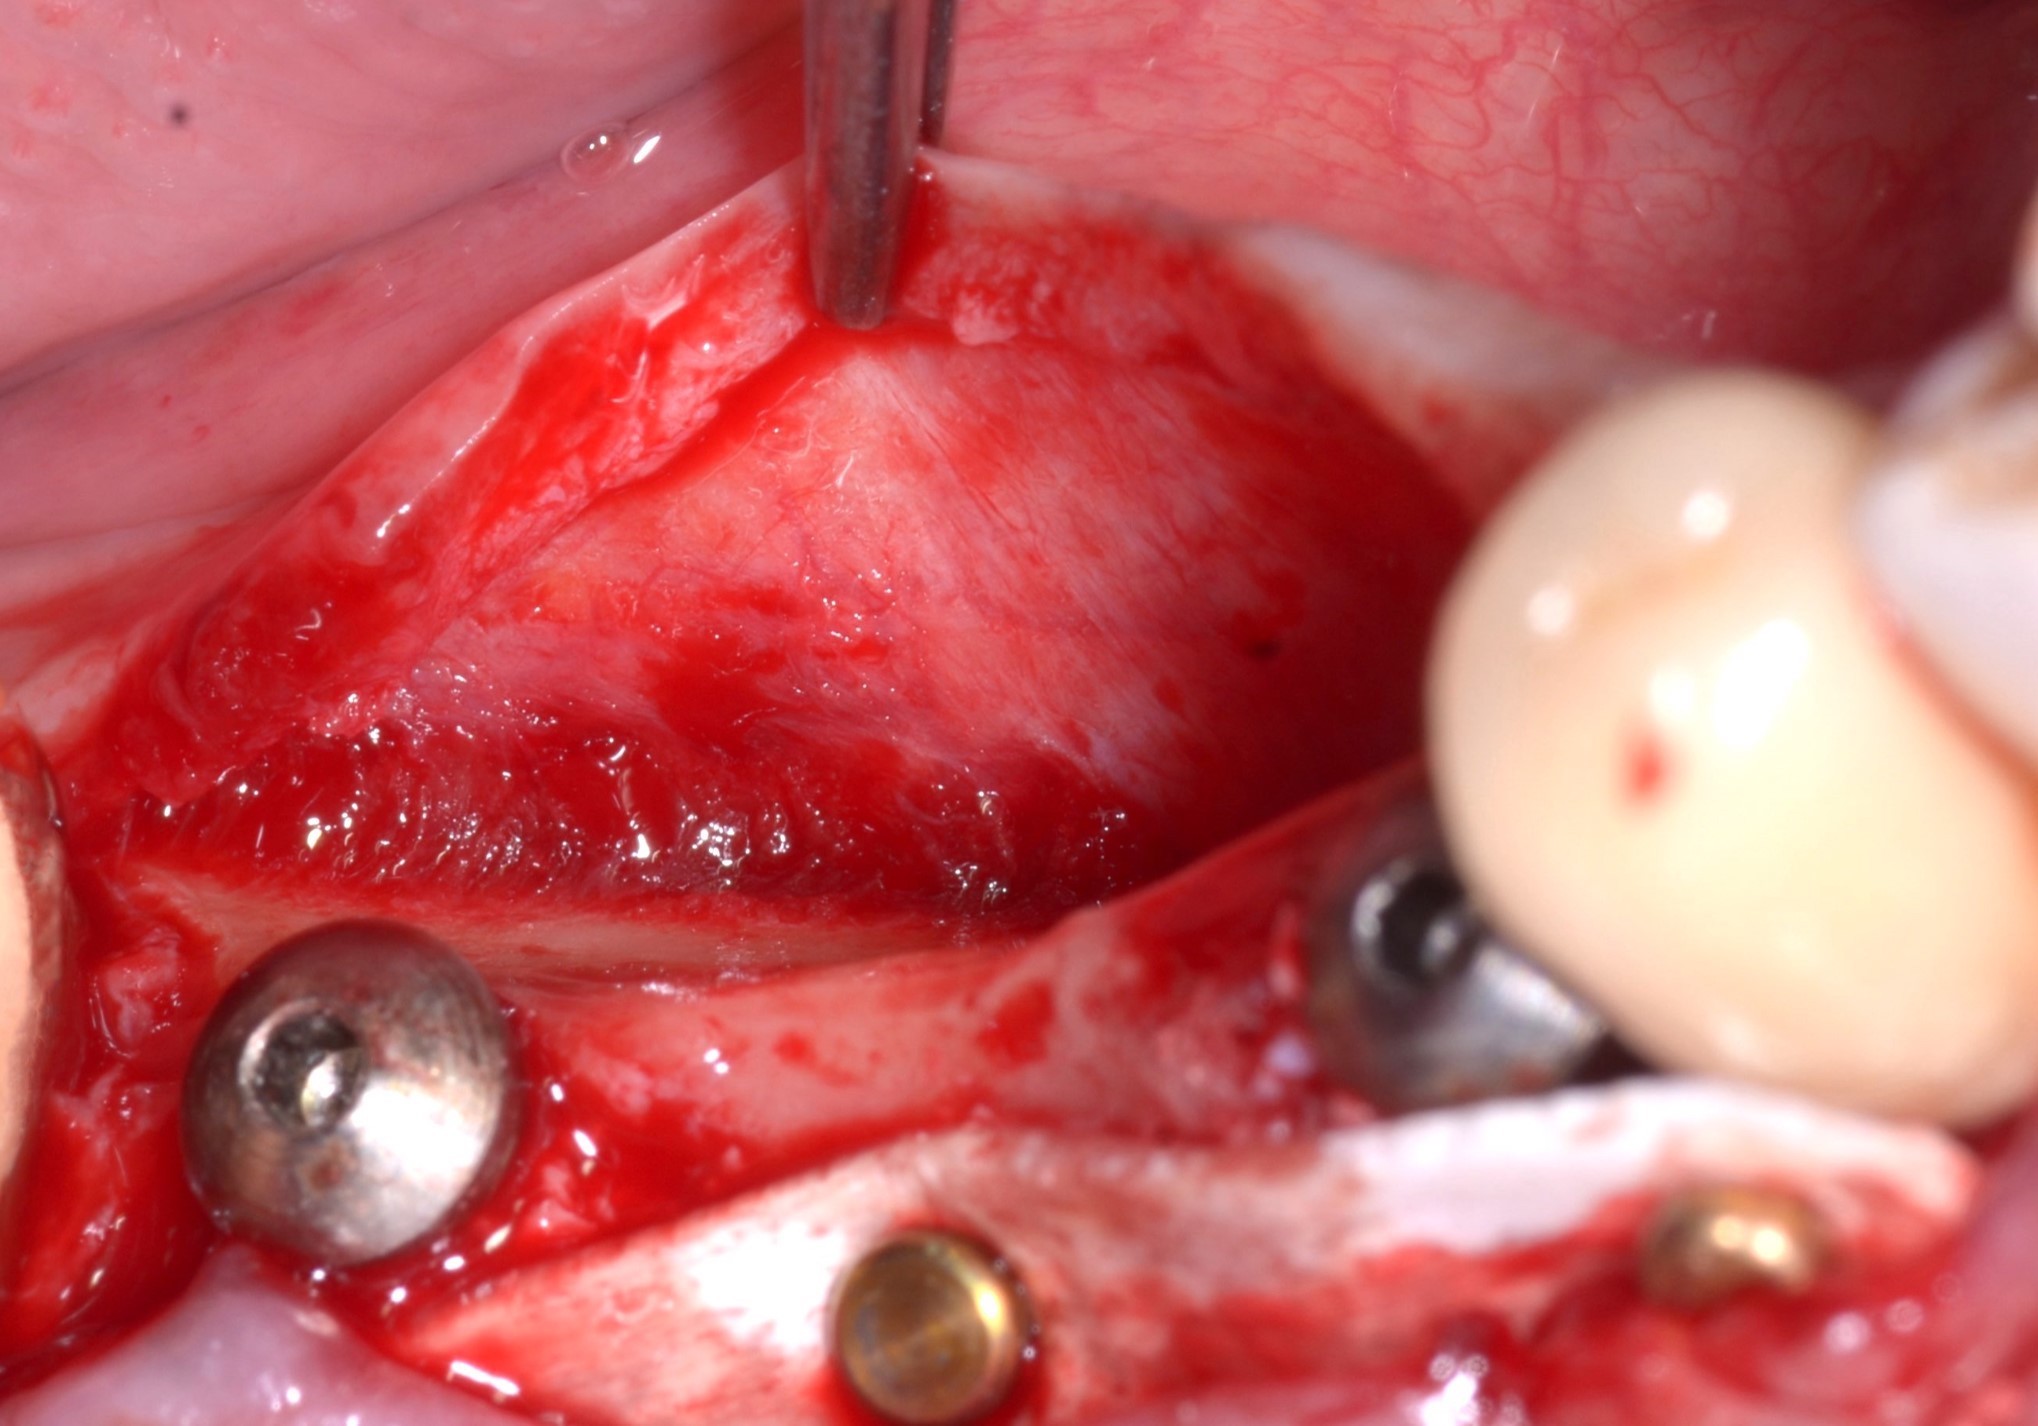

El día anterior a la operación, se administró a la paciente antibioticoterapia con amoxicilina y ácido clavulánico 1 g comprimidos cada 12 horas. El día de la intervención se realizó profilaxis antibiótica 1 hora antes del inicio con 1 g de amoxicilina + ácido clavulánico y se administró anestesia local con articaína + adrenalina 1:200.000. Posteriormente, se realizó una incisión lineal de grosor completo en la cresta a lo largo de toda la extensión del defecto, combinada con dos incisiones de liberación vestibular, también de grosor completo. A continuación, se realizó una cuidadosa disección del colgajo subperióstico para obtener una visibilidad adecuada de la zona del defecto. Después se preparó el túnel implantario en las posiciones 44 y 46 y se insertaron los implantes, de 5 x 10 mm y 4,1 x 8,5 mm, respectivamente (Figs. 2 y 3).

Fig. 2. Esqueletonización del defecto y preparación del túnel del implante.

Fig. 3. Inserción del implante y medición de la atrofia horizontal de aproximadamente 5,5 mm.

Clínicamente, se observó una atrofia horizontal de la cresta alveolar de 5,5 mm entre los dos implantes. Para resolver la atrofia horizontal, se decidió realizar un procedimiento ROG utilizando gránulos heterólogos y la Lámina Cortical Flex. Esta última se modeló en primer lugar utilizando una plantilla estéril (Fig. 4).